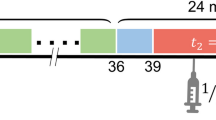

For investigation of the impact of dynamic PET timeframe truncation on modelling outcomes, the 120-min dataset was truncated by 20, 40, 60, 70, and 80 min.

The impact of truncating PET scan duration on kinetic model outputs

The intraclass correlation coefficients (ICC) of K1, VT and BPTC were calculated for each truncation of the 120-min dynamic PET duration (Fig. 4). K1 ICC values were unaffected by truncations in scan duration (Fig. 4a). The VT ICC demonstrates greater stability in brain outcomes for different truncations compared with heart outcomes (Fig. 4b). The improved brain performance versus the heart maybe due to the decreasing effect of the apparent quasi-irreversible kinetics on 2TCM (Fig. 1). Conversely, for BPTC, a truncation greater than 20 min begins to reduce the number of fittable datasets (defined as the organ data for one animal) and parameter stability in the brain (Fig. 4b and c), but less so in the heart. The kinetic constant values for the hypoperfused left ventricular anterior wall were the most affected by truncation of PET scan duration with the highest number of non-fittable datasets. When assessing the ICC of truncated data within the naive and MI cohorts separately, K1, VT and BPTC ICC results are overall comparable (Supplementary Fig. 4). However, a truncation greater than 20 min still results in loss of fittable datasets.

The ICC of 2TCM parameters for invasive AIF function, IDIF and PET frame truncation in all datasets. a The ICC for K1 calculated using the different conditions in naive and MI rats is shown as dots (left Y axis), with the lines detailing the number of datasets (rats) where calculation of K1 was possible (right Y axis). b The same analysis is shown for VT and c) BPTC. n = 15 (6 naive animals and 9 MI animals)